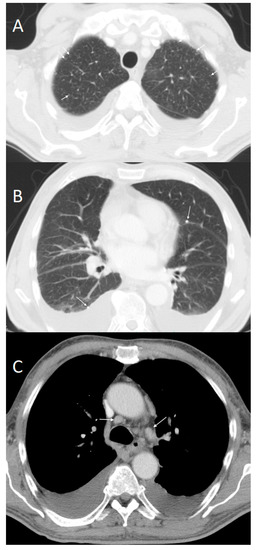

2. Case Report

3. Autopsy